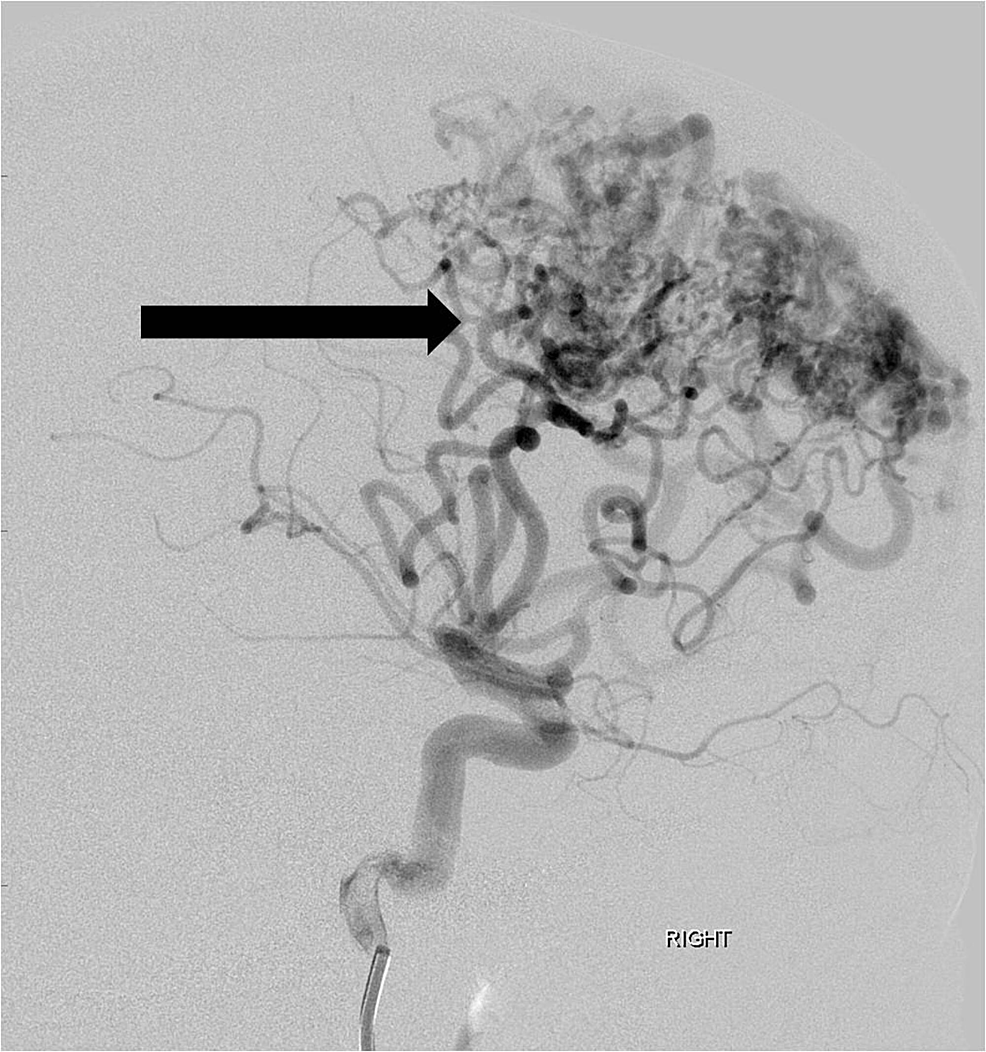

He was then transferred for a higher level of care to a high-volume Comprehensive Stroke Center. Cerebral angiography showed a non-ruptured left frontal AVM that was fed by anterior and middle cerebral artery branches (Figure 2).

He was scheduled for a pre-operative embolization the following week in anticipation of subsequent surgical resection. Under general anesthesia, four separate arterial feeding pedicles from the right anterior cerebral artery were catheterized (Figure 3).